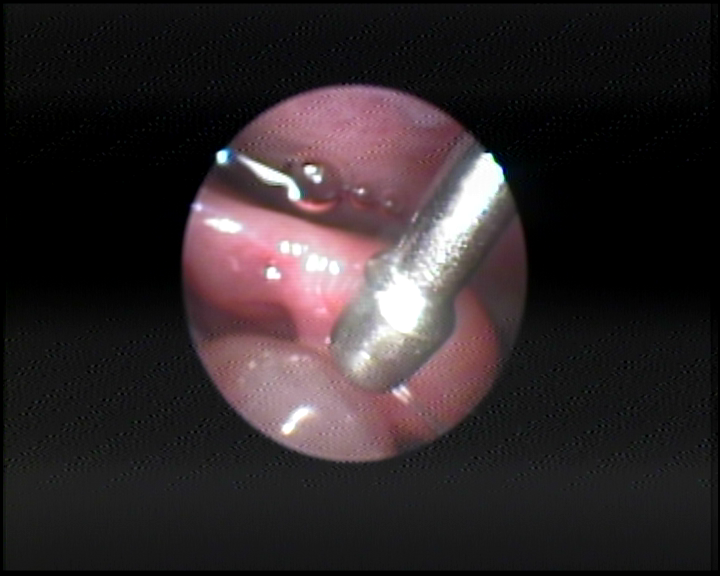

Polyp mũi bên trái Polyp mũi bên phải

Polip hốc mũi phải

Bn ĐTM - 61 tuổi

Bn NPT - 41 tuổi

Polyp mũi là một trong những biến chứng của bệnh viêm mũi xoang mạn tính, là một bệnh lý có dạng u phát triển trên bề mặt niêm mạc của các cấu trúc bên trong hốc mũi như cuốn giữa (Middle Turbinate), khe mũi giữa (Middle Meatus), hoặc cửa lỗ xoang hàm, xoang sàng hoặc trong lòng các xoang. Về mặt giải phẫu Polyp thường xuất hiện cả hai bên hốc mũi, có nhiều múi, có thể quan sát được khi nội soi, có màu hồng nhạt, hoặc hơi xám, bóng nhắn, mềm và có thể di động lắc nhẹ khi có tác động của một lực tiếp xúc. Vị trí hay gặp nhất là Polyps ở khe giữa, có thể phát triển kích cỡ lấp đầy khe này và lan rộng bít kín hốc mũi; Polyp có thể triển ra phía sau che kín lỗ mũi sau và thõng xuống vòm họng.